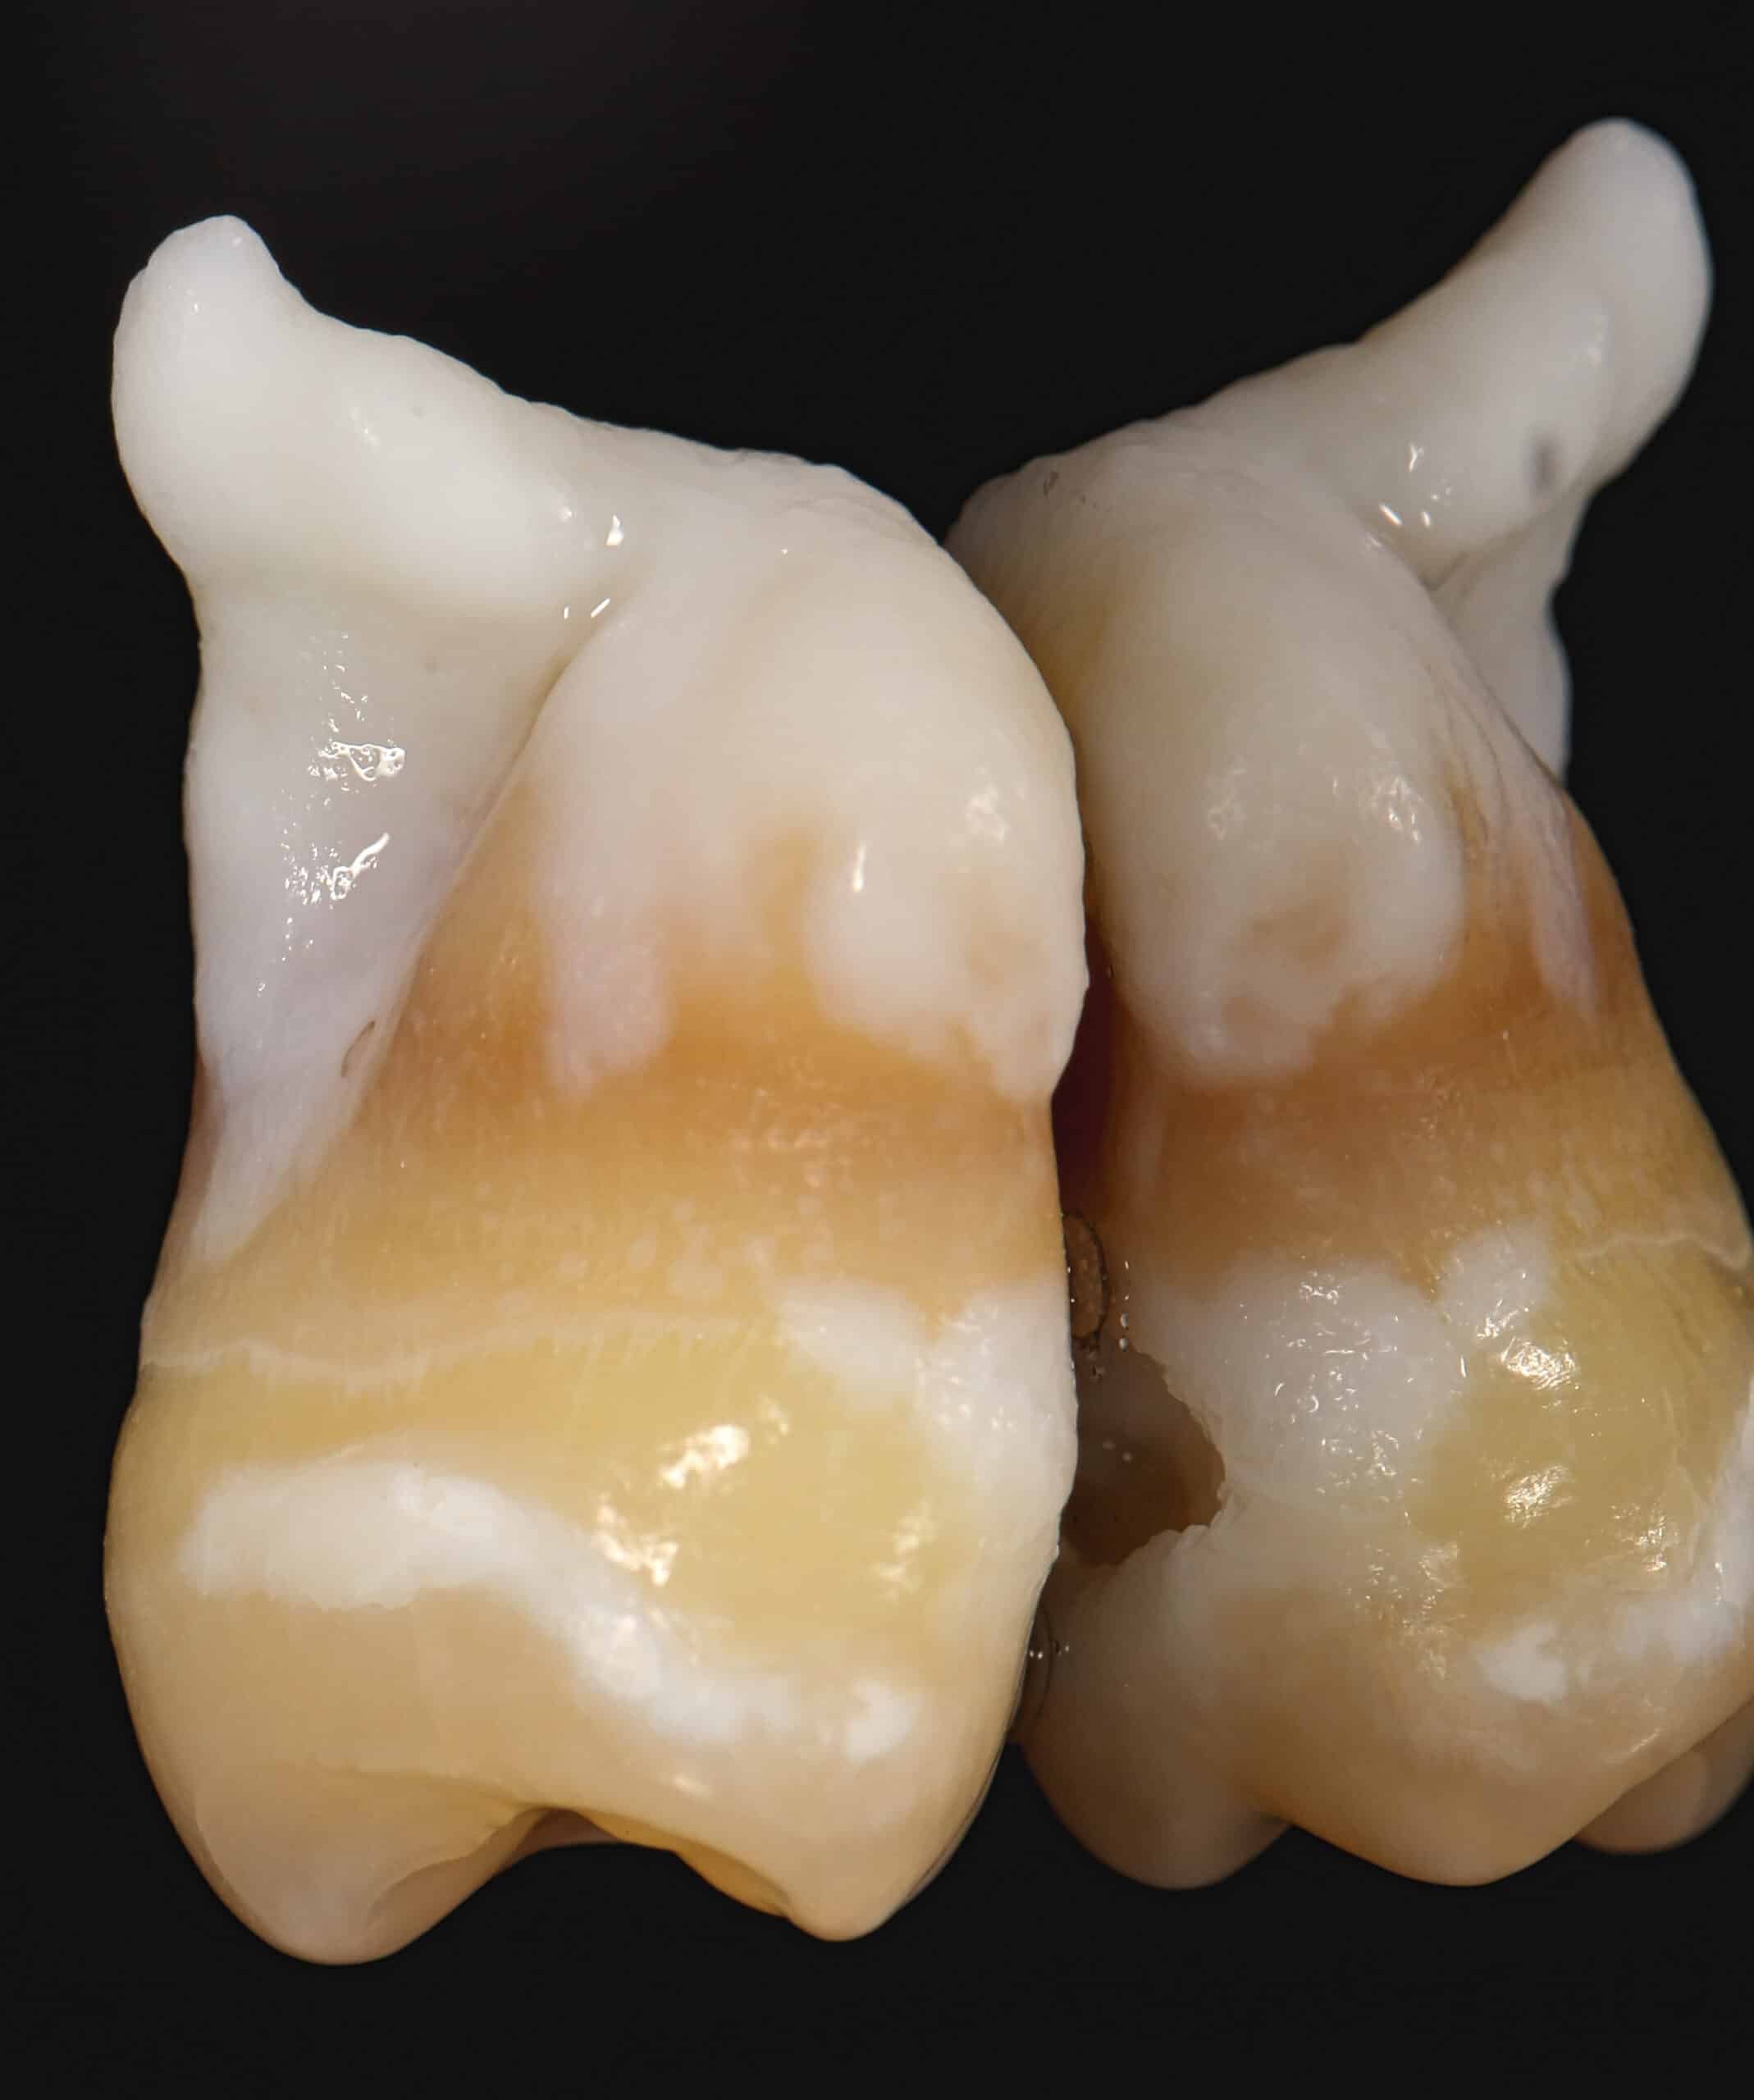

Wisdom teeth can be very hard to clean with a tooth brush. For that reason they can develop cavities. If the cavity grows to reach the nerve of the tooth, the patient will experience pain. It’s usually best to extract wisdom teeth with large cavities.

The actual tooth extraction is not painful most of the time. However, the patient will feel some pressure. Usually, wisdom tooth extraction in the lower jaw will cause more post-op discomfort than a wisdom tooth extraction in the upper jaw. That’s because the bone in the lower jaw is much denser compared to maxillary bone.